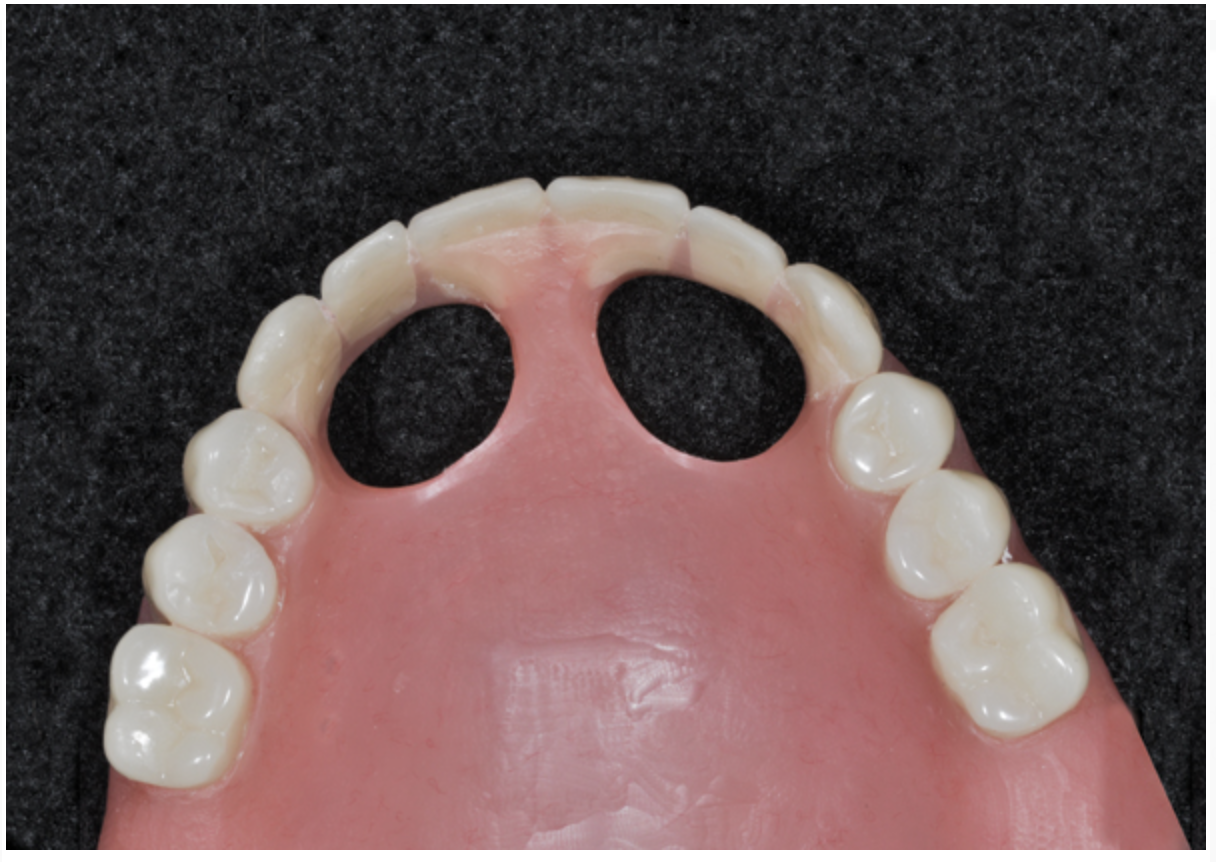

The definitive prosthesis is delivered between 6 and 12 months later, allowing time for tissue remodeling. Typically, the preferred definitive restoration is a highly esthetic acrylic hybrid prosthesis secured over a CAD/CAM–milled titanium bar designed for a full acrylic wrap on the intaglio surface of the restoration with pink restorative material that simulates gingiva. This type of restoration is cost-effective and easily repaired or modified. Alternative options include fixed zirconium bridges, fixed zirconium framework with individual cemented crowns, and porcelain-fused-to-metal restorations. Regular recall every 3 to 4 months is paramount for maintenance and to identify and rapidly treat potential biologic or biomechanical complications.

Dental rehabilitation with the All-on-4 treatment concept is often a life-changing event for edentulous and terminal dentition patients that results in unprecedented quality of life improvements (Figure 17 through Figure 20).

Fig 19. Patient smile shown 3 years post-treatment.

Figure 19

Fig 20. Patient intraoral condition 3 years following delivery of maxillary and mandibular All-on-4 definitive prosthesis.

Figure 20